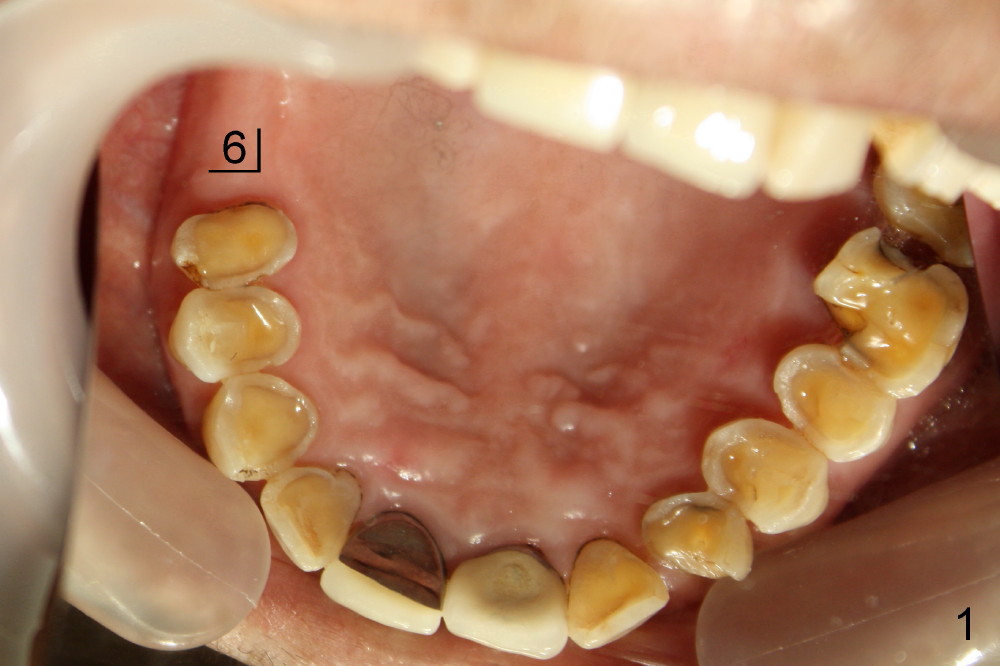

几个月前右下六根尖周炎,根管治疗无效,Amoxicillin引起全身过敏性皮炎,最后拔除。术后六周伤口愈合,牙槽骨有些吸收(图四),通过骨扩张,植入6x17mm植牙(图五,牙槽骨好像不再萎缩了,与图四相比),伤口挺密合,不需要缝线,但是不是天衣无缝,细菌食物还是会进入伤口造成感染。服用抗生素好像不是个好主意(过敏史),灵机一动:使用periodontal dressing盖住植牙(图六)。但是术后病人抱怨局部肿痛,最后还是服用灭滴灵。术后第九天,患者回诊所左上七牙冠粘固,顺便拆除右下periodontal dressing(图六),dressing下面伤口愈合了吗?还是象图二那么糟(婚纱后面新娘漂亮吗)?